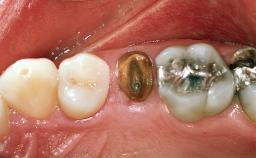

A 27-year-old man was referred to the Department of Oral Surgery and Stomatology (University of Bern, Switzerland for implant therapy in the anterior maxilla. The patient was healthy and did not smoke. His tooth 21 was apically malpositioned and ankylosed due to a dental trauma during adolescence. The preoperative examination included an esthetic risk assessment (Martin and coworkers 2006), which revealed a number of high-risk elements, most important among them the patient’s high smile line and the non-harmonious gingival margins of the maxillary anterior dentition. Tooth 21 was associated with significant gingival recession. Tooth 11 required treatment to eliminate or mask severe discoloration from previous root canal treatment. A periapical radiograph confirmed the ankylosed condition of root 21 and disclosed characteristic signs of advanced external root resorption, also showing that both central incisors had been exposed to root canal treatment. Neither tooth showed indications of apical pathology.